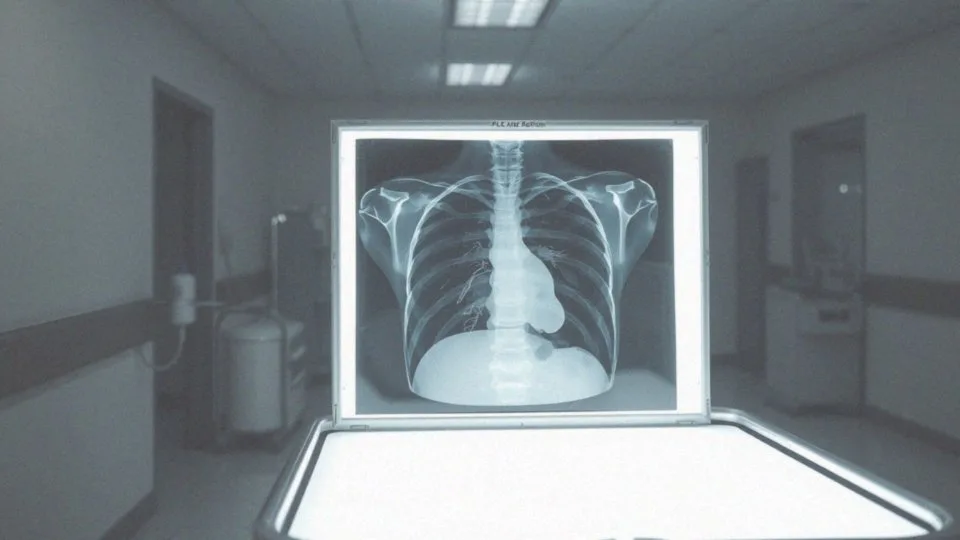

W diagnostyce zrostów w płucach kluczowe okazują się badania obrazowe, które umożliwiają dokładną ocenę stanu zdrowia pacjenta. Wśród najczęściej wykorzystywanych metod znajdują się:

- rentgen klatki piersiowej,

- tomografia komputerowa.

Rentgen pozwala dostrzec zmiany w strukturze płuc, takie jak zgrubienia opłucnej czy inne nieprawidłowości. Odpowiedni opis wyników RTG jest istotny, ponieważ interpretuje obrazy i wskazuje na potencjalne zmiany chorobowe. Tomografia klatki piersiowej natomiast to metoda bardziej zaawansowana, która pozwala uzyskać szczegółowe obrazy płuc. Dzięki niej lekarze zyskują możliwość precyzyjnego określenia lokalizacji oraz rozległości zrostów, co jest niezwykle istotne w rozumieniu stanu zdrowia pacjenta. Takie informacje pomagają ustalić, czy zrosty są jedynym problemem, czy też występują inne patologiczne zmiany.

Diagnozowanie zrostów opłucnowych rozpoczyna się od szczegółowego badania lekarskiego. Specjalista ocenia ruchomość klatki piersiowej oraz osłuchuje szmer pęcherzykowy. W diagnostyce kluczowe są badania obrazowe, takie jak:

Rentgen umożliwia dostrzeżenie zgrubień opłucnej i innych nieprawidłowości. Natomiast tomografia dostarcza wyraźnych obrazów, które pozwalają dokładnie określić położenie i rozmiar zrostów. Gdy uzyskane wyniki nie są wystarczające do postawienia jednoznacznej diagnozy, lekarze mogą zlecić drenaż opłucnej. Ten zabieg pozwala na pobranie płynu z jamy opłucnej, co jest niezbędne do dalszej analizy, a badanie pobranego płynu dostarcza cennych informacji o stanie zdrowia pacjenta, w tym możliwości wykrycia infekcji, na przykład gruźlicy.